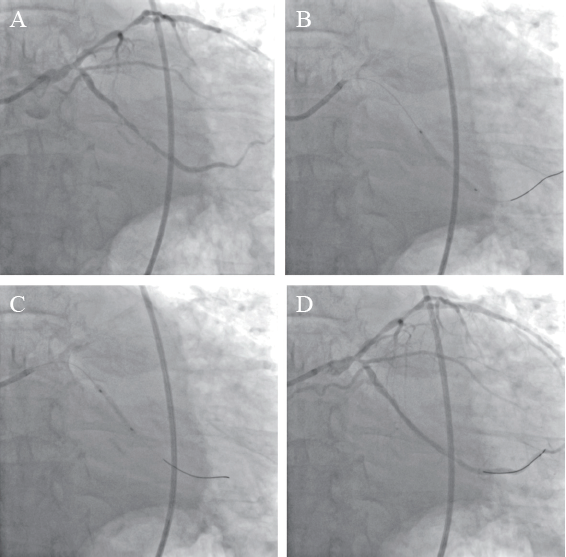

图1 一例NSTEMI患者术前CAG图

A:右肩位显示前降支近段可见约90%狭窄,中段可见约80%狭窄,远段可见约90%弥漫性狭窄,第一对角支近段可见约70%狭窄;B:正头位显示回旋支中段可见约90%弥漫性狭窄;C:蜘蛛位显示左主干末端可见约50%狭窄,回旋支开口可见约80%狭窄;D:正头位显示右冠状动脉近段可见约80%狭窄,中段可见约80%狭窄,远段可见约90%狭窄,后降支开口可见约80%狭窄,中段可见约90%狭窄,左室后支近段约90%弥漫性狭窄;箭头所示狭窄处